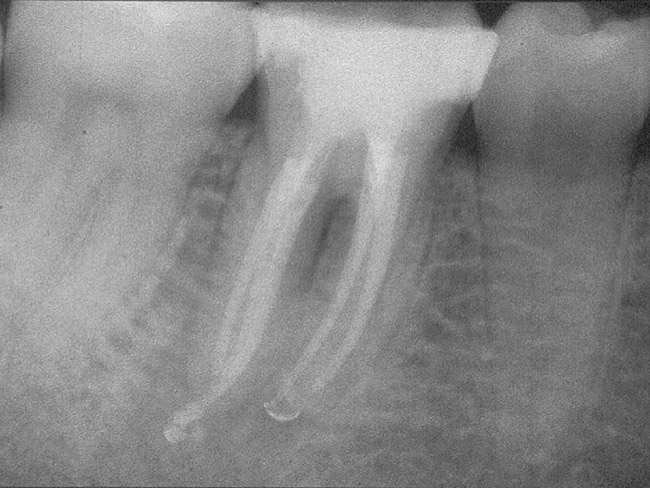

Figure 4a  Tooth No. 30 Nonsurgical root canal treatment had been completed 5 years before. The periapical radiograph revealed periradicular radiolucencies (periapical and in the furcation area).

Figure 4a

Figure 4b  The patient was asymptomatic, and periodontal probing depths were within normal limits; however, a new crown restoration was planned. Nonsurgical endodontic re-treatment was initiated. The intracoronal picture shows the previously treated 4 canals with infected gutta-percha filling.

Figure 4b

Figure 4c  Under high magnification, a furcation canal (Figure 4C) and a third distal canal (Figure 4D) were located.

Figure 4c

Figure 4d  Under high magnification, a furcation canal (Figure 4C) and a third distal canal (Figure 4D) were located.

Figure 4d